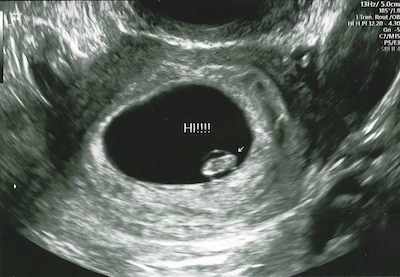

The first time I saw you, you looked like a little dot, but you were there! It made me feel happy to see you and gave me all the butterflies in my stomach.